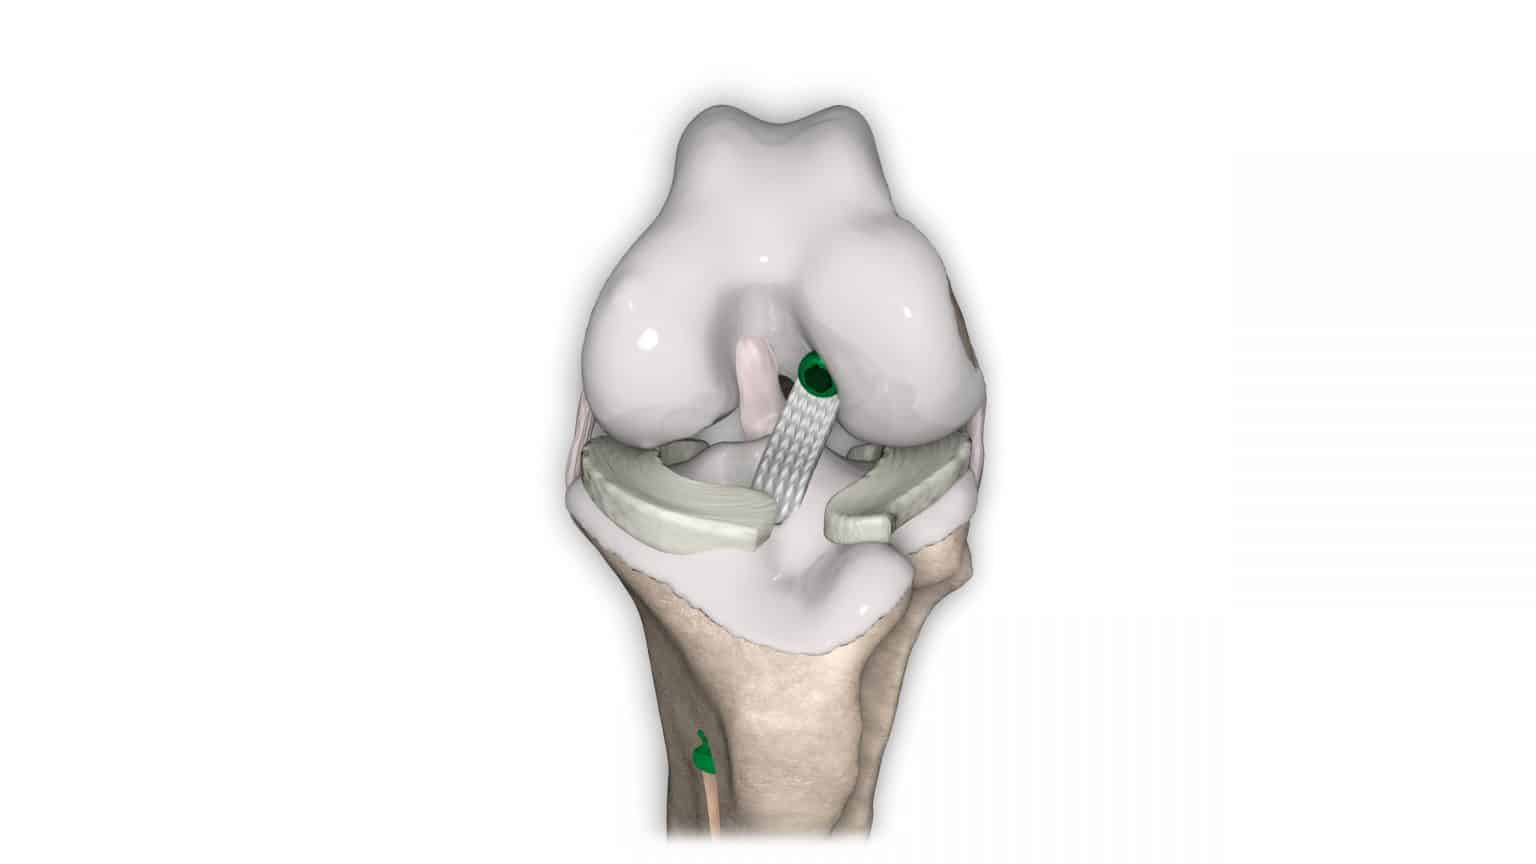

V případě ruptury kraniálního zkříženého vazu umožňuje ExtraTape® extraartikulární rekonstrukci co nejblíže izometrii původního vazu, čímž rychle a trvale stabilizuje koleno bez uzlů a zvlnění, což je slabina tradičnějších technik extraartikulární stabilizace. Ty jsou zde nahrazeny pevným ukotvením kosti pomocí interferenčního šroubu.

Řešení, které respektuje původní anatomii, obnovuje funkci postiženého vazu a je dostupné v rámci otevřené nebo artroskopické chirurgie.